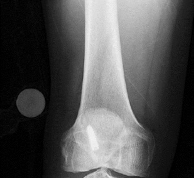

Question 11

A 9-year-old boy sustains a distal femur fracture. Radiographs demonstrate a fracture line propagating along the physis and exiting through the metaphysis, producing a small metaphyseal bone fragment (Thurston-Holland fragment). Based on the Salter-Harris classification, what type of fracture is this, and what is the typical expectation regarding growth arrest?

Explanation

A fracture that propagates through the physis and exits through the metaphysis (creating a Thurston-Holland fragment) is a Salter-Harris Type II fracture. It is the most common physeal fracture pattern. Because the germinal layers of the physis remain attached to the epiphysis, the general prognosis for growth is good. However, one must recognize that Type II fractures of the distal femur inherently carry a high risk of growth arrest (up to 40-50%) compared to other locations.